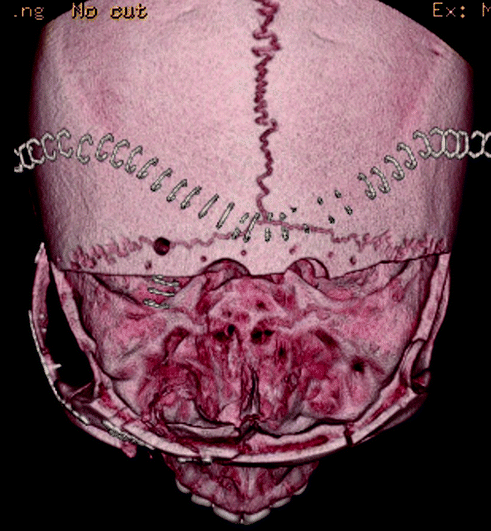

Fig. 19.13

Postoperative three-dimensional reconstruction demonstrating cranial decompression, reconstruction of zygomatic, maxillary, orbital bandeau, and orbital roof fractures

Fig. 19.14

Fig. 19.15